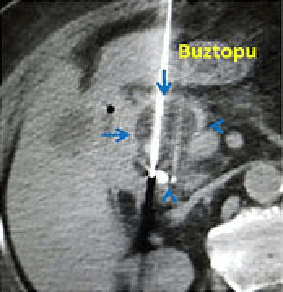

Pankreas başı kanseri (kırmızı oklar) olan hastamıza 2 probla kriyoablasyon yapılıyor.

İşlem sırasında çekilen tomografide kriyoabalasyonun oluşturduğu buztopu izleniyor.